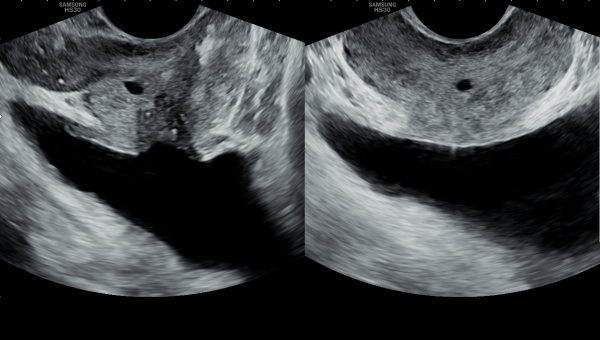

내원당일 경직장 전립선 초음파 검사상 정낭의 낭종이 커져 있고 정낭내 결석이 관찰되는 측면 경직장 초음파 사진입니다.

수년동안 사정관과 정관등의 순환장애로 내원 당일 고환의 초음파 검사상 고환의 섬유화가 관찰되는 초음파 사진입니다.

This is an ultrasound image of the testes taken on the day of the visit, showing testicular fibrosis likely caused by years of circulatory disturbances in the ejaculatory ducts and vas deferens.